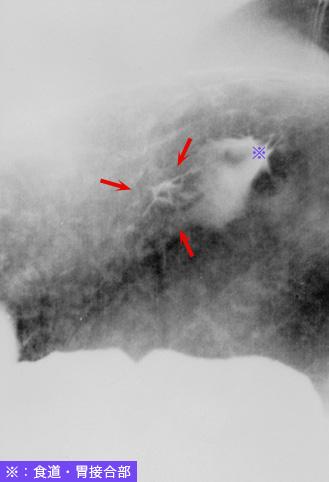

疾病(病理主体)的分类恶性上皮性肿瘤/腺癌

部位(按器官分)胃(部位)/喷门

检查方法X线

肿瘤的肉眼分类0型(表在型)/IIc型(IIc)

肿瘤最大直径1~9

肿瘤的深度m